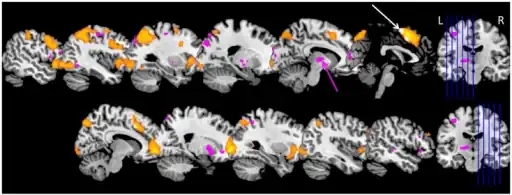

| Overview of suggested brain regions and networks involved in KLS [2] | |

In patients with KLS, MRI and CT scans show normal brain morphology. When SPECT is performed, hypoperfusion can often be observed in the brain,[19] particularly in the thalamic and frontotemporal areas.[9] The hypoperfusion is significantly diminished between episodes.[20] Serum biology, c-reactive proteins and leptins, the hormonal pituitary axis, and protein in the cerebral spinal fluid (CSF) are normal in KLS patients.[21]

It is not known what causes KLS, but several mechanisms have been proposed. One possible explanation is hypothalamic or circadian dysfunction.[6] The thalamus probably plays a role in the out-of-control sleeping,[22] and patients with diencephalic–hypothalamic dysfunction caused by tumors experience symptoms similar to those of KLS patients.[6] Specifically, the medial temporal regions of the thalamus may be involved,[23] although examinations of KLS patients have not consistently found abnormalities in this area.[9] The temporal lobe also appears to play a role in the condition, possibly causing cognitive difficulties. The apathy and disinhibition found in some with KLS suggest that the condition may include frontal lobe dysfunction as well. The involvement of the thalamus, temporal lobe, and frontal lobe of the brain suggests that there is a multifocal, localized encephalopathy. There are also persistent subclinical abnormalities in some with KLS.[22]